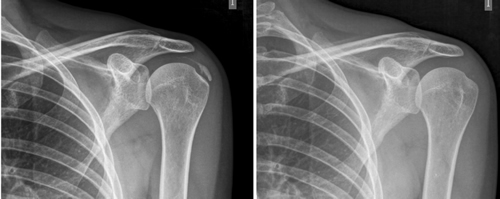

Resultados: Edad media: 54,6 años (n = 138); mujer (73,1 %; n = 101); proporción mujer/hombre 3: 1; tendón supraespinoso (94,6 %; n = 124); subescapular (5,4 %; n = 14); hombro izquierdo (55,1 %; n = 76), hombro derecho (44,9 %; n = 62); bilateral 1,4 % (n = 2); diestros 96,3 % (n = 133); antecedentes personales: tabaquismo (19,5 %; n = 27), diabetes (7,2 %; n = 10). El tiempo de enfermedad promedio fue de 6,08 meses. Dolor agudo-subagudo (menos de 3 meses) 47,1 %; (n = 65), dolor crónico (más de 3 meses) 52,9 % (n = 73). Tipo radiológico: formativo 75,3 % (n = 104), resortivo 24,7 % (n = 34). Número promedio de sesiones: 20. Complicaciones del tratamiento 2,8 % (n = 4): intolerancia/eritema/quemadura. Ocupación: administrativo 39,8 % (n = 55), trabajos manuales 60,2 % (n = 83). El dolor inicial EVA de 7,3 puntos disminuyó significativamente (p = 0,0000) después del tratamiento a 2,7. El tamaño promedio inicial de las calcificaciones fue de 10,7 mm y disminuyó significativamente (p = 0,0000) después del tratamiento a 3,8 mm. Cambio de calcificación: tasa de éxito/curación 55,7 % (n = 77), tasa de mejora 20,2 % (n = 28); tasa de fracaso del 23,9 % (n = 33). La limitación funcional disminuyó de un 10,8 % a un 2,1 %.

Results: Mean age 54.6 years (n = 138). Female (73.1 %; n = 101); female to male ratio 3:1. Supraspinatus tendon (94.6 %; n = 124), subscapularis (5.4 %; n=14); left shoulder (55.1 %; n = 76), right shoulder (44.9 %; n = 62). Bilateral 1.4 % (n = 2). Right handed 96.3 % (n = 133); Personal history: smoking (19.5 %; n = 27), diabetes (7.2 %; n = 10); disease time averaged 6.08 months; acute-subacute pain (less than 3 months) 47.1; (n = 65), chronic pain (greater than 3 months) 52.9 % (n = 73). Radiological type: formative 75.3 % (n = 104); resorptive 24.7 % (n = 34). Average number of sessions: 20.5. Treatment complications 2.8 % (n = 4): intolerance/erythema/burn. Occupation: administrative 39.8 % (n = 55), manual jobs 60.2 % (n = 83).

Average initial pain 7.3 points (VAS scale), significantly decreased (p = 0.0000) post treatment to 2.7. Initial average size of calcifications 10.7 mm and significantly decreased (p = 0.0000) post treatment to 3.8 mm. Change of calcification: success/cure rate 55.7 % (n = 77), improvement rate 20.2 % (n = 28); failure rate 23.9 % (n = 33). Functional limitation decreased from 10.8 % of patients to 2.1 %.